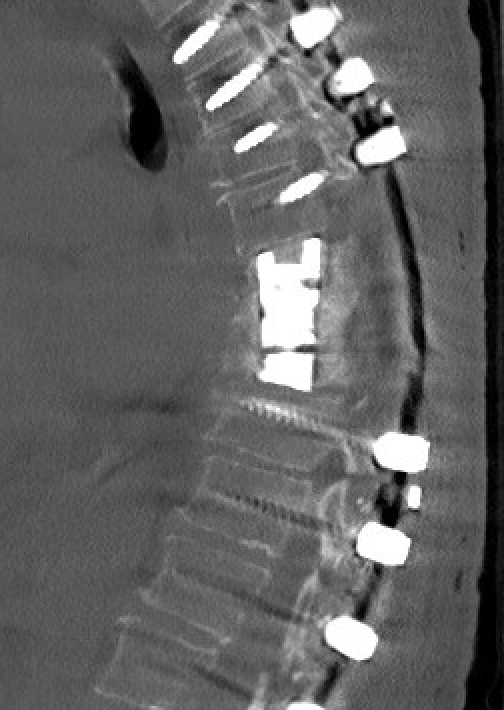

Postop X-ray corrected scoliosis

A patient after spinal fusion with near complete reduction of curvature.